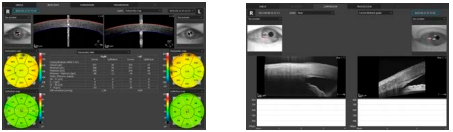

Передняя камера

Чтобы провести обычное исследование состояния фронтальной камеры не нужны вспомогательные линзы. Благодаря этому доктор, обследующий пациента, оперативно производит сканирование. Сведение результатов для обоих глаз дает возможность идеально точно провести оценку ситуации на фронтальном участке. Вспомогательный адаптер, идущий в комплекте с инструментом, расширяет диапазон использований при обследовании передней камеры.